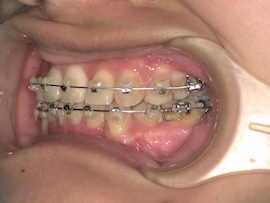

写真は撮っていないのでさらに1ヶ月後、

急に親知らずが出てきましたね。(笑)

無事に牽引ができたので、内側の装置も外れました。予定していたよりもかなり早く、牽引を始めてから約5ヶ月の時点です。